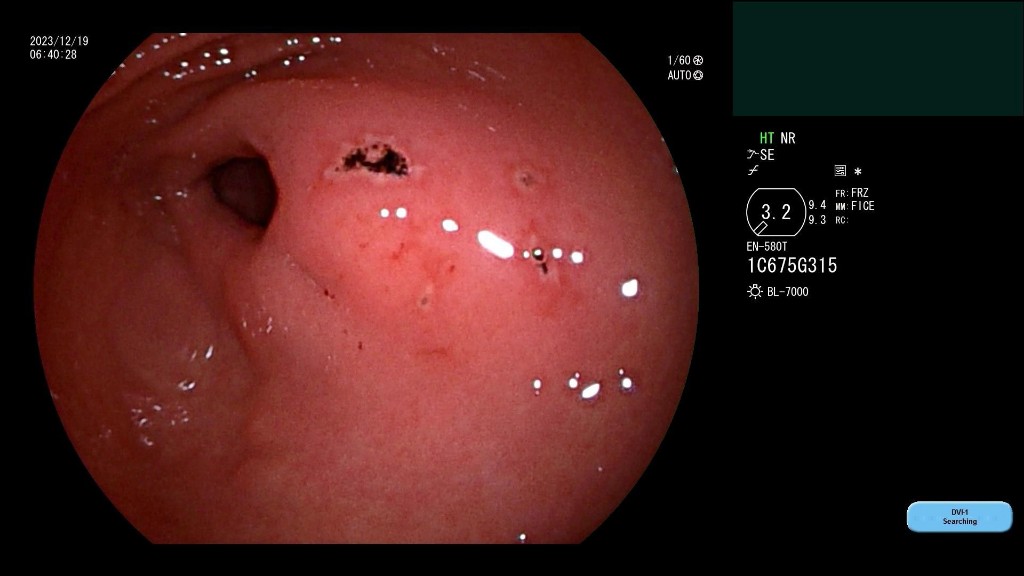

在了解患者情况后,西安市红会医院消化疾病诊疗中心消化内科副主任施育鹏以及相关医护人员当即从家中赶往医院,在此期间消化内科开启消化道出血绿色通道,为患者做腹部CT,同时联动麻醉科医生进行麻醉评估。到达医院后,为避免肠道穿孔,施育鹏医生借助小肠镜,在贲门处调转钢钉方向,用小肠镜外套管包裹钢钉头并取出,整个过程仅用时20分钟,术后患者情况稳定。

完成一场急诊小肠镜,取出小肠内的异物,需要具备多少条件?此次手术的成功,展现出西安市红会医院消化内科小肠镜水平的成熟。西安市红会医院消化疾病诊疗中心消化内科主任韩霜介绍,由于小肠弯曲,误吞的异物如枣核、绣花针等如果从十二指肠进入小肠,随时有穿孔风险,需要通过肠镜取出,而小肠镜手术需要在全麻下进行。在严重的情况下则需要通过剖腹手术移除。

19日在消化道出血绿色通道开启后,红会医院及时联动麻醉科为患者进行麻醉评估,消化内科医护人员则迅速赶往医院进行治疗,为患者争取最佳治疗时间。同时,在手术进行中,如果出现小肠穿孔情况,消化内科配备相应的内镜下止血条件,避免患者剖腹手术的风险。消化内科的医疗团队接触小肠镜案例多、技术纯熟,可以为患者提供专业的医疗服务。